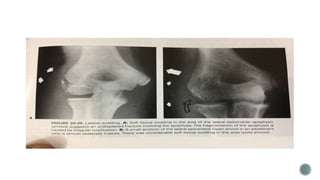

 Weiss modiefied

 Type 1 – displaced less than

2mm

 Type 2 – displaced more than

2mm but have intact cartilaginous

hinge

 Type 3 – displace more than

2mm and no intact cartilaginous